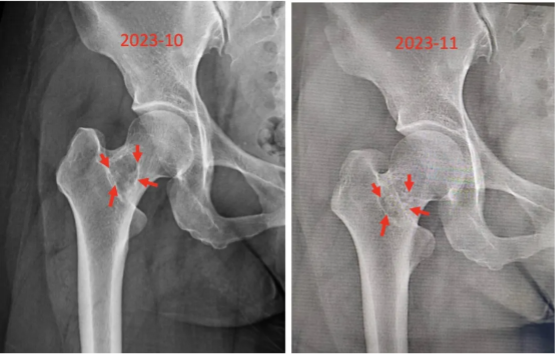

图7:术后通道植骨满意

图8:术后一个月复查,骨折愈合良好